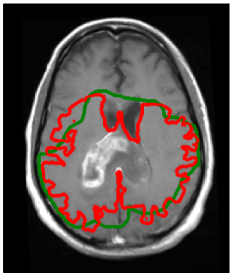

Refer to caption

Figure 4: Comparison of manually defined targets (light/dark green) and model derived targets (orange/red). In the clinical treatment plan, the light green volume was prescribed to 60 Gy, the dark green volume to 46 Gy. The yellow contour shows the abnormality on T2-FLAIR.

3.1 Target volume definition

Figure 4 shows the clinical target volume (dark green contour) and the boost volume (green contour) drawn manually by the physician, i.e. these contours were the basis for the treatment plan that was actually delivered to the patient. The prescribed dose to the boost volume was 60 Gy, the prescribed dose to the CTV was 46 Gy. The boost volume is defined based on a 2 cm isotropic extension of the contrast enhancing lesion. The CTV is defined via a 1.5 cm expansion of the T2-FLAIR abnormality. Both volumes were subsequently trimmed manually to account for anatomical boundaries (dura, ventricles, falx, and tentorium cerebelli). The dose distribution of the 3D conformal treatment plan delivered to the patient is shown in figure 6d.

Using the tumor growth model, the target volume can be defined as an isoline of the tumor cell density. This is illustrated here for the tumor cell density shown in figure 3a obtained for the parameter value Dw/Dg=100subscript𝐷𝑤subscript𝐷𝑔100D_{w}/D_{g}=100. The red and the orange contours in figure 4 show the CTV and the boost volume derived from the tumor growth model, respectively. In this example, the target defining isolines are chosen such that the total enclosed volume is equal to the manually delineated target. In the following two subsections, we discuss the differences between manual and model-derived target volumes in detail.

In the manual delineation of the CTV used in the clinical plan, it is incorporated that the falx represents an anatomical barrier for the migration of tumor cells. Hence, the isotropic target expansion was trimmed manually. In the tumor growth model, the falx is modeled via a layer of CSF and is automatically accounted for through the assumption that tumor cells only migrate within white and gray matter. However, the corpus callosum connects the two hemispheres of the brain. The tumor growth model describes the migration of tumor cells through the corpus callosum (see figure 3 and 5a). As a consequence, the target volume based on the growth model is extended into the contralateral hemisphere. Figure 5a shows the tumor cell density overlaid on the coronal T1 gadolinium image. This illustrates the three-dimensional modeling of tumor spread via the model, including areas superior to the corpus callosum. This is not consistently accounted for in the manual CTV. In the manually drawn target volumes, the target is slightly extended into the contralateral hemisphere on the slices that show the corpus callosum, but not on the slices located superiorly and inferiorly (figure 5b). In the model derived target volumes, the target is extended further into the contralateral hemisphere, and the spread of tumor cells in superior-inferior direction beyond the corpus callosum is modeled.